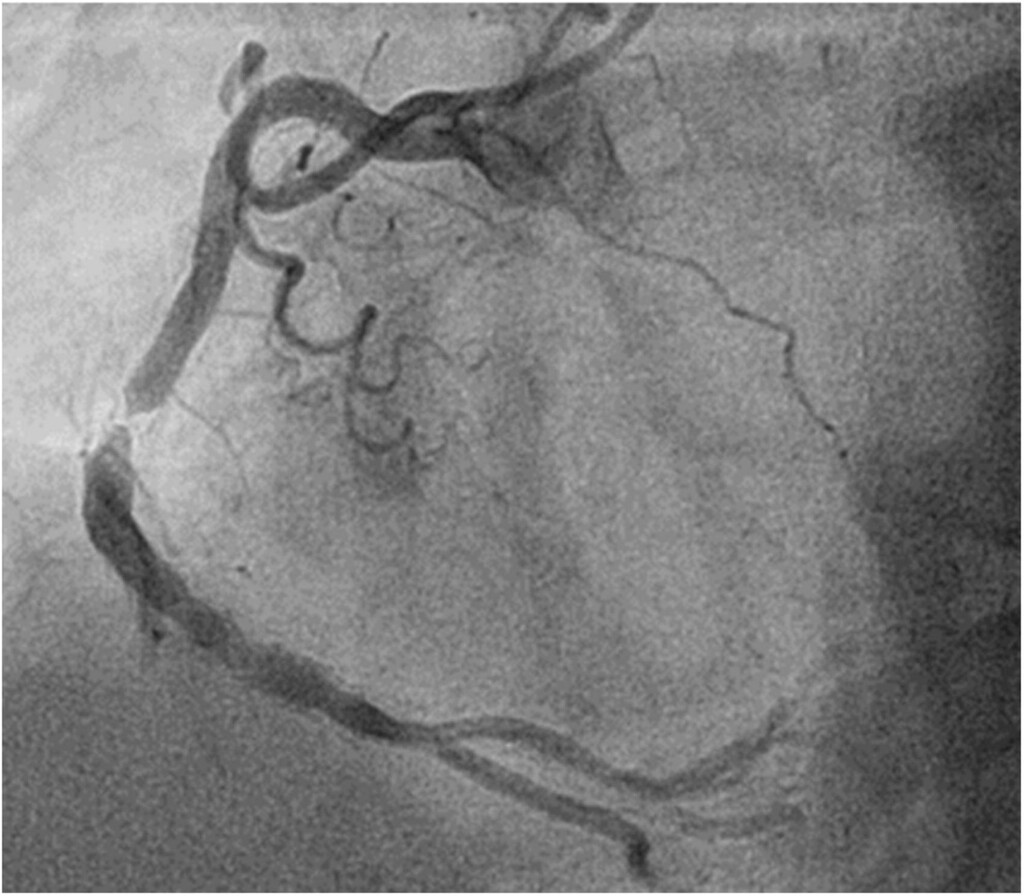

【者王可米/北】心血管疾病年位居人十大死因,其中冠疾病是心肌梗塞猝死的主因。透心管手置入心支架,能有效打通阻塞血管,恢心供血。然而,非一永逸,後仍存在一在支架再阻塞。

支架再阻塞指血管在置入支架後月至年再次窄。主要原因包括,血管皮胞度增生,使支架膜厚、硬化一步化,及不良生活如抽菸、血糖控制不佳等,致血管再次受。管新一代**物支架(DES**已大幅降低再窄率(5-10%),但此仍不容忽。